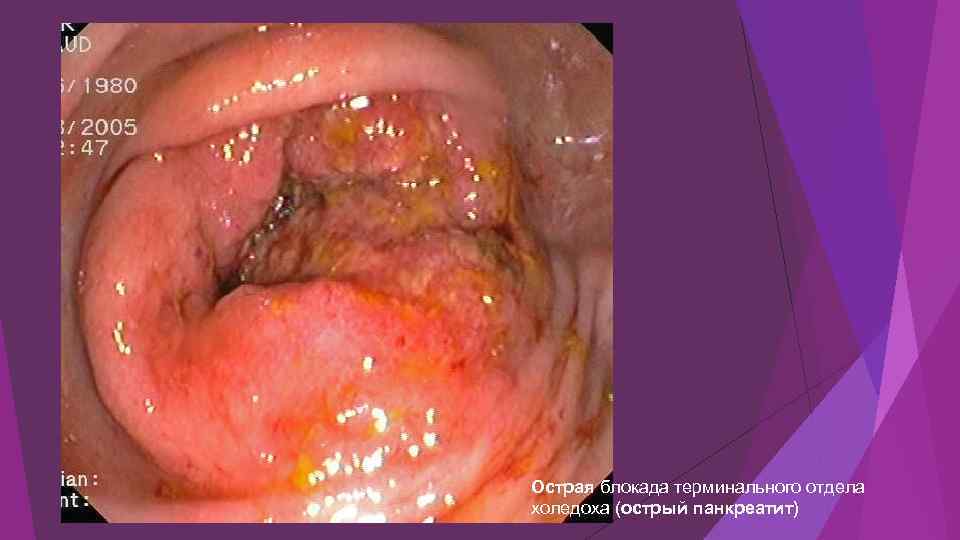

Острая блокада терминального отдела холедоха (острый панкреатит)

Острая блокада терминального отдела холедоха (острый панкреатит)